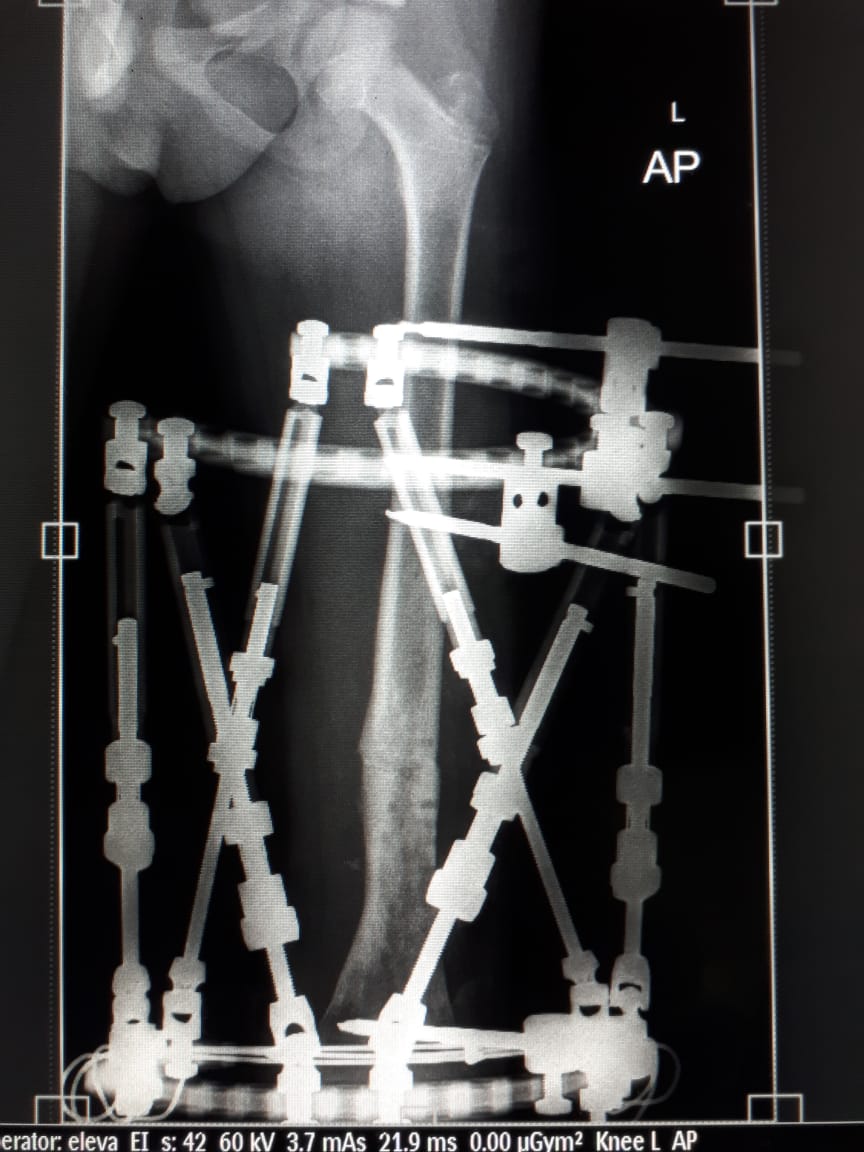

وأضاف : عقب اكتمال الاجراءات أجريت العملية بتركيب جهاز التثبيت الخارجي الحلقي (TSF) على الفخذ و إصلاح الميلان بالفخذ بشكل كامل مع إزالة القطع العظمية الملتهبة بعملية واحدة ، حيث أن هذه المرة الأولى التي تستخدم فيها هذه التقنية بمستشفى أبها للولادة والأطفال.

وبعد استقبال الطفل تم تقييم حالته و أُخضِعت الحالة لعمل الفحوصات الطبية اللازمة ، وأظهرت الأشعة المقطعية و المغناطيسية امتداد الالتهاب حيث تبين أنه يشمل ثلث عظمة الفخذ.